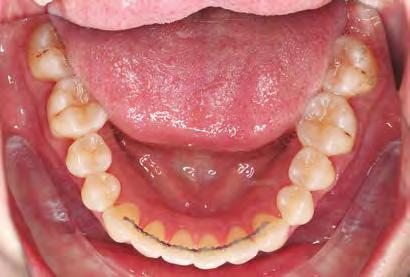

–MARPE, una alternativa a la disyunción en el paciente adulto, por el Dr. Enrique Solano y cols. [88]